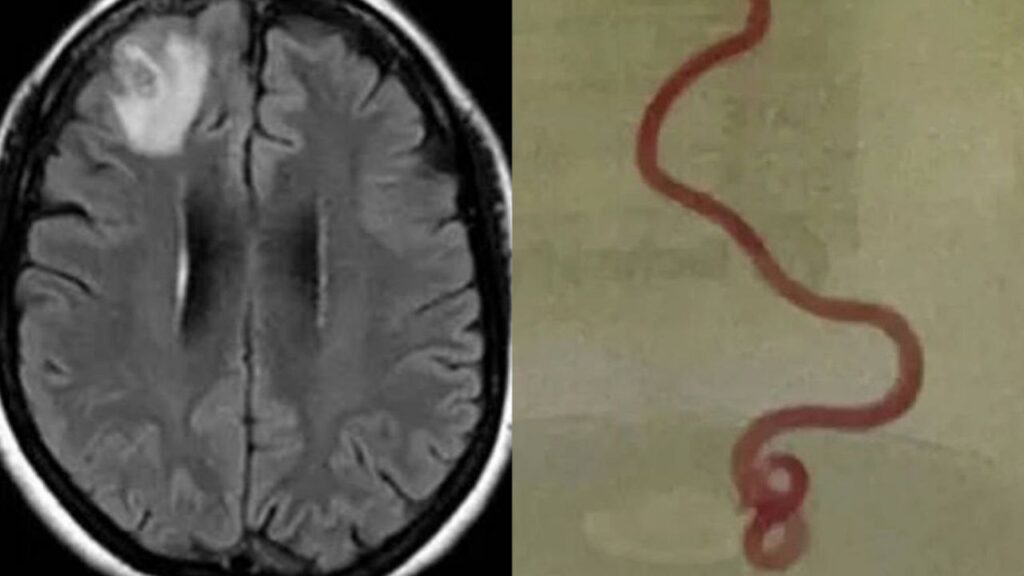

Médicos australianos lograron por primera vez en la historia extraer una lombriz intestinal viva del cerebro de una mujer.

Es la primera vez que una lombriz intestinal viva es extraída del cerebro humano.

“Se trata del primer caso en el mundo de Ophidascaris o tiña parásita procedente de una serpiente y que infecta un ser humano”, detallaron los galenos.

La revista Emerging Infectious Diseases destacó el primer caso de una lombriz intestinal extraída del cerebro de una mujer.